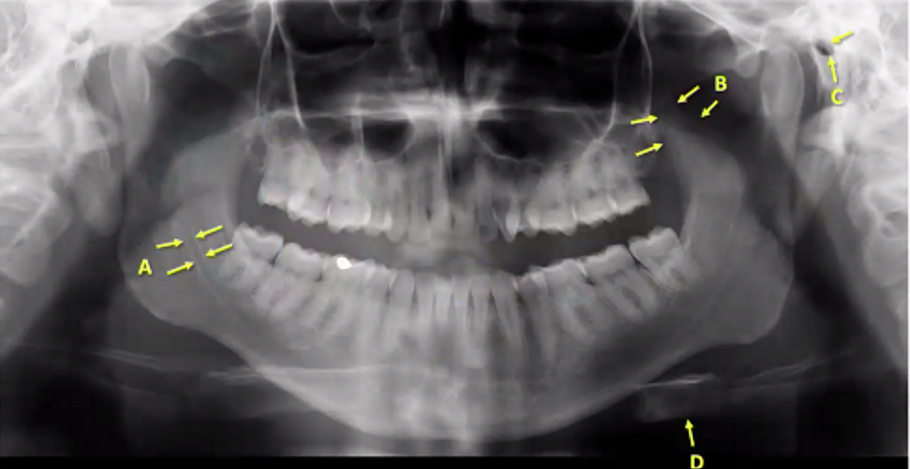

A

ethmoid sinuses

B

globe/eye

C

inferior concha

(meatus is the bone, here is inbetween so soft tissue)

D

Maxillary sinus